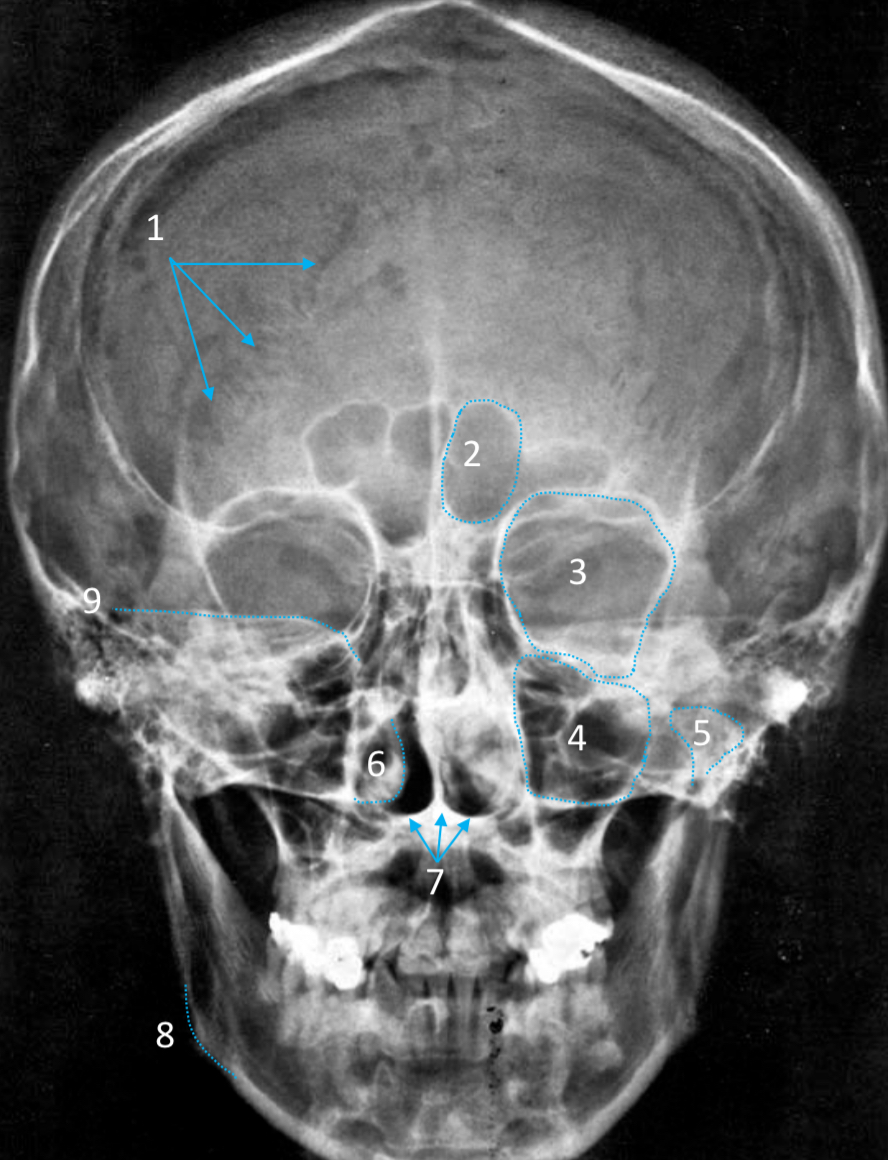

Frontal sinus

ID structure

Pituitary fossa

ID structure

Frontal sinus

ID structure

Orbital margin

Orbit

Maxillary sinus

ID structure

Mandibular condyle

ID structure

Inferior nasal concha

ID structure

Hard palate

ID strucutre

Gonial angle

ID strucutre

Petrous ridge

ID structure

Groove of middle meningeal a.

ID structure

Roof of orbit

ID structure

Frontal sinus

ID structure

Pituitary fossa

ID structure

Petrous ridge

ID structure

Sphenoid sinus

ID structure

Hard palate

ID structure

Mastoid air cells

ID structure

Zygomatic arch

ID structure

Mandibular condyle

ID structure

External auditory meatus

ID structure

Mastoid air cells

ID structure

Foramen magnum

ID structure

Foramen ovale

ID structure

Foramen spinosum

ID structure